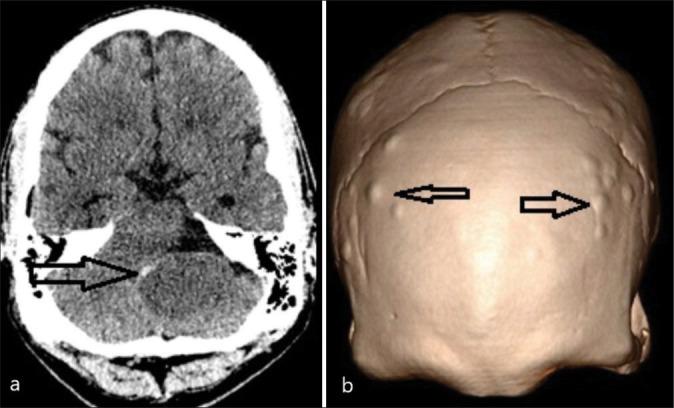

颅咽管瘤是起源于鞍区和鞍上区域的良性肿瘤。虽然异位肿瘤确实会发生,但通常是由于局部扩散或复发性肿瘤。单纯的异位小脑脑桥角(CPA)或第四脑室肿瘤极为罕见,并且已发现与遗传性疾病家族性腺瘤性息肉病(FAP)显著相关。

病例描述

迄今为止,仅报道了4例与FAP相关的异位CPA颅咽管瘤病例。在此,我们报告第5例以FAP为背景的异位CPA颅咽管瘤病例。同时也对先前描述的病例进行了阐述。

结论

以FAP为背景的CPA肿瘤应考虑颅咽管瘤的鉴别诊断,同样,原发性异位CPA颅咽管瘤可能提示潜在的APC基因突变。